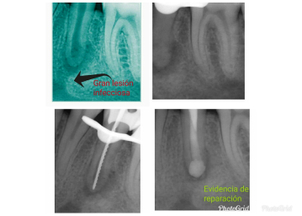

Lesión infecciosa tratada por la Dra. Katherine Ruiz

La endodoncia es un tratamiento que permite salvar un diente muy dañado o infectado a través de una reparación que no supone como primera opción, la extracción de la pieza. De acuerdo a la Clínica Mayo, el término “endodoncia” hace referencia al proceso de limpiar los conductos en el interior de la raíz de un diente.

Indicado para tratar piezas dentales con caries muy profundas que provocan la inflamación o la necrosis de la pulpa dental, que no es más que la parte más interna del diente donde se encuentran vasos sanguíneos y nervios.